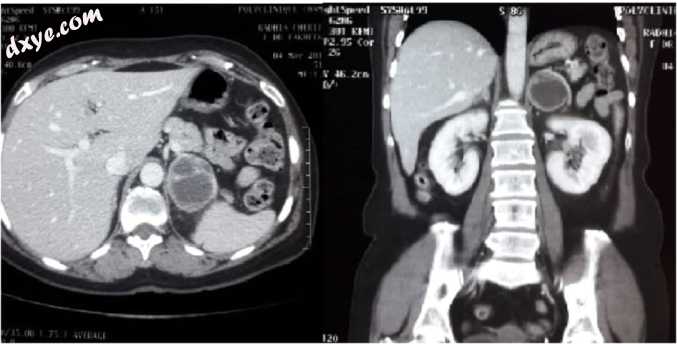

一名无病史的41岁男性在过去2年间出现间歇性腹部绞痛,心悸发作和出汗。体格检查发现他的血压升高了170 / 90mm Hg,没有明显的腹部肿块。腹部CT显示左肾上腺囊肿为6cm×4.3cm x 4.3cm,内部有细小分隔(图1)。实验室研究发现,嗜铬细胞瘤的血浆去甲肾上腺素为1087 pg / ml,间肾上腺素为372 pg / ml。血清钾,血浆醛固酮,肾素和尿皮质醇正常。根据临床,生化和放射学发现,怀疑有一例囊性嗜铬细胞瘤。腹腔镜经腹膜左肾上腺切除术(图2)。在整个手术过程中,没有任何明显的血液动态型畸形。手术持续了70分钟。术后住院期间,他的血流动力学保持正常,血压约为120 / 70mm Hg。没有疼痛或手术部位感染发生。病人于第3次首次手术当天出院。组织病理学证实诊断为囊性嗜铬细胞瘤,其PASS评分为3(无转移潜力)且切缘阴性(图3)。

图 1

CT扫描显示左肾上腺有一个6cm的囊肿,内部有细小分隔。